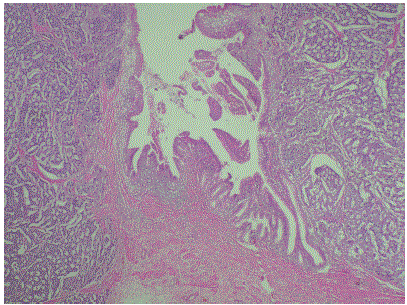

Figure 5. Microphotograph showing neuroendocrine tumor at the ampulla. The pancreatic duct is also seen. (Magnification, x40).